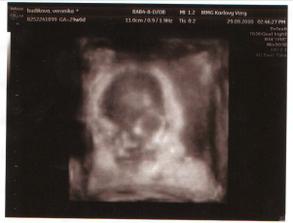

29. 9. 2010 (29tt + 0)

Dnes jsme s taťkou absolvovali UTZ ve 30tt. Malej se dneska kupodivu dobře vyspal, tak se předváděl jak jen mohl. Krásně se na nás smál a pak, jak říkal pan doktor, cosi povídal, ale tomu jsme nikdo nerozuměl 😀 Dnes Ondrášek ukázal i svůj doposud utajovanej obličejík, jakoby věděl, že jej sonda již celý nevykreslí a fotka nezachytí. Takže fotečka bohužel není nic moc :-//// ale je na ní vidět hezounký nosánek a rtíky 🙂)) místo očíček jsou jen velká kola :-//// Jinak dle UTZ vše v naprostém pořádku, plodové vody máme akorát, malej je evidentně spokojený a je již hlavičkou dolu. Nožičky měl dnes u mě v bříšku vlevo vedle pupíku a byl v bříšku stočený do písmene L. Nakonec nám pan doktor ještě pouštěl tlukot srdíčka a ukazoval nám jak mu krásně tluče a také jsme si prohlédli plný žaludek a močový měchýř Ondráška 🙂)) No byl dneska prostě malej opět kouzelnej 😵) Už se na něj s tatínkem mooooc těšíme.

Pro úplnost údajů - naměřený průměr hlavičky je 77mm, bříška 233mm a stehnní kost je dlouhá 54mm. Ondrášek odpovídá nyní už 29+1, já jsem dle MS dnes 29+0. Váhový odhad k porodu při dnešních 1240 gramech je dle pana doktora v rozmezí od 3,2kg do 3,5kg. Takže žádné čtyřkilové dítko by se snad konat nemělo . Ufff ....